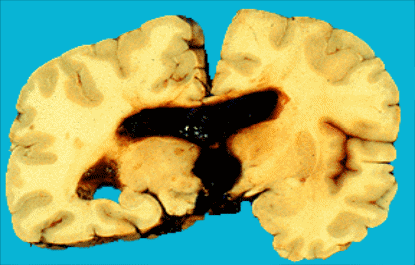

Рис. 1 Субдуральная гематома.

Субдуральные кровоизлияния всегда имеют травматическую природу. Источником их являются вены, впадающие в верхний сагиттальный синус, сосуды мозжечкового намета. Супратенториальные субдуральные кровоизлияния характеризуются нарастанием гипертензионно–гидроцефального синдрома через 2-4 дня "светлого промежутка", мидриазом на пораженной стороне, стойкой девиацией глазных яблок в сторону поражения, гемипарезом на противоположной стороне, судорогами, комой, выбуханием и пульсацией родничков, брадикардией, нарушением терморегуляции.

При нераспознанной гематоме через 7-10 дней происходит ее инкапсуляция с последующей атрофией мозговой ткани. Лечение нейрохирургическое. Субтенториальные субдуральные кровоизлияния (кровоизлияния в заднюю черепную ямку) характеризуются особой тяжестью. С момента рождения нарастают симптомы сдавления ствола мозга: ригидность затылочных мышц, анизокория, стойкое отведение глаз в сторону, грубый нистагм, тонические судороги. Прогрессируют брадикардия, расстройство дыхания, вялость, гипо- и арефлексия, расстройство сосания и глотания.

Лечение: поверхностная субдуральная гематома дает благоприятный исход, если своевременно произведен субдуральный прокол, удалена кровь и снижено внутричерепное давление. Хирургическое лечение необходимо, если прокол неэффективен.